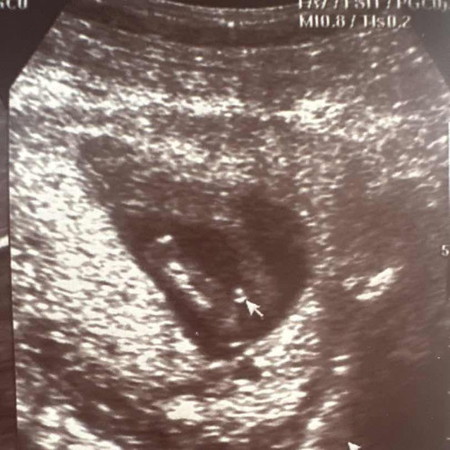

สอบถามแม่ๆ ค่ะ มีสิทธิ์เป็นเพศหญิงมั้ยค่ะ

แบบนี้จะเป็นเพศอะไรค่ะ

อยากได้ ผญ ค่ะ